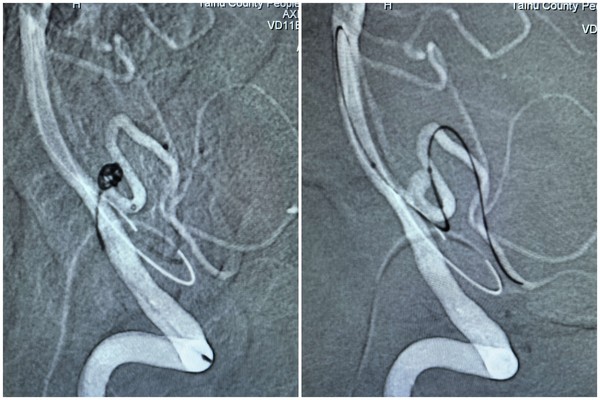

手术当天,在 DSA 设备实时引导下,介入医生先为患者进行右侧股动脉、右侧桡动脉穿刺置管,成功建立双通道。随后,通过股动脉通路,利用翻山技术将支架微导管置入右侧小脑后下动脉;同时通过桡动脉通路,将弹簧圈微导管精准送入动脉瘤腔内。团队先填入几枚不同规格的弹簧圈,再沿支架微导管释放一枚颅内支架,实现对动脉瘤的完全覆盖。术中造影显示,动脉瘤已完全隔绝,基底动脉、右侧小脑后下动脉血流通畅,未出现血管狭窄或栓塞迹象,整个手术历时 2 小时顺利完成。

术后 6 小时,患者意识清醒,四肢活动正常,经神经功能评估未出现任何并发症;术后复查头颅磁共振,也未发现急性脑梗死。“不用开颅,睡一觉手术就做完了,县医院的技术真是高超!” 患者对此次微创介入治疗的效果赞不绝口。